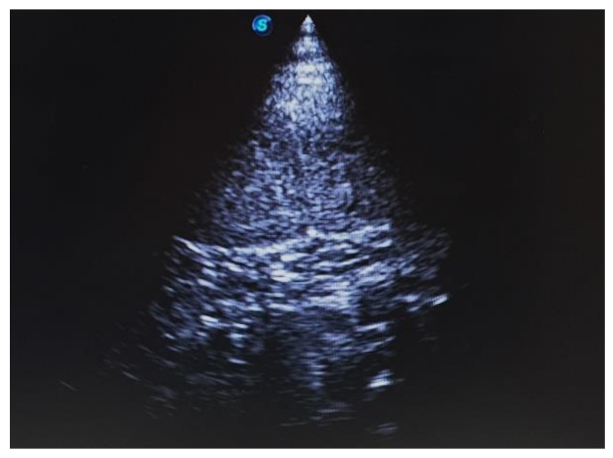

An 8.5-year-old intact female lion (Panthera leo) with a history of vomiting, lethargy, and anorexia was referred to our institution. On physical examination under anesthesia using medetomidine (0.034 mg/kg, IM; SedaSTART, Yuhan, Seoul, Korea) and ketamine (1.67 mg/kg, IM; YUHAN KETAMINE 50 Inj., Yuhan, Seoul, Korea), the lion weighed 180 kg and showed a rectal temperature of 40 °C. Blood analysis showed mild neutrophilic leukocytosis (27.45 × 109/L; mean of captive lions, 12.2 × 109/L). Abdominal ultrasonography revealed a distended uterus with echogenic fluid (Figure 1). Based on the clinical signs and results of the above examinations, the lion was tentatively diagnosed with pyometra.

Figure 1. Uterine horn in a lion (Panthera leo) with pyometra. Presence of markedly distended uterine horn with echogenic intraluminal material.